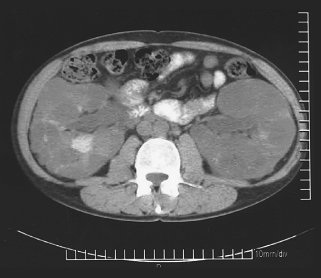

<p><span>A 38-year-old woman was hospitalized because of bilateral flank pain and gross hematuria. Her medical history included autosomal dominant (adult) polycystic kidney disease (ADPKD). Her...